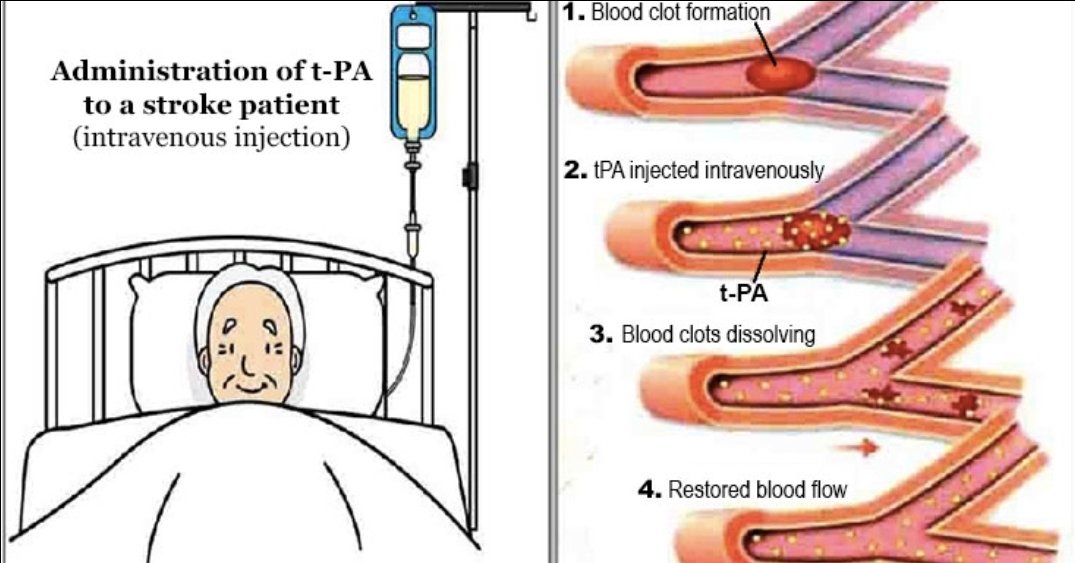

♦️مذيب جلطات وريدي

(فقط اول ٤ ساعات ونصف)

♦️مذيب جلطات وريدي

(فقط اول ٤ ساعات ونصف)